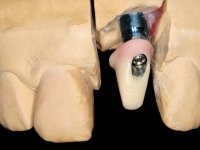

Na fase inicial, foi proposto à paciente fazer a exposição cirúrgica do implante e após avaliação clínica tomar decisões protéticas. Colocado o parafuso de cicatrização e feita a cicatrização dos tecidos moles, foi constatada uma posição inadequada do implante. Perante o dramatismo da situação foi proposto à paciente a remoção do implante e após regeneração tecidular colocar um novo implante. Esta proposta foi recusada pela paciente e foi sugerido por esta a reabilitação provisória do implante. Nesse sentido foi então feita nova proposta, desta feita, reabilitando o implante. Foi sugerido a confeção de um coto aparafusado e sobre este a colocação de uma coroa de acrílico com componente coronário e gengival. Passados 6 anos com o tratamento provisório a paciente surge na consulta com um abcesso no dente 1.1. Feita a análise clínica e imagiológica decidiu-se extrair os dentes 1.1 e 2.2, submergir o implante, colocar dois implantes no local dos 1.1 e 2.2 e fazer regeneração tecidular adequada. A temporização seria feita com uma ponte provisória de 3 elementos aderida com uma rede aos dentes vizinhos. Após osteointegração seria reabilitada definitivamente com uma ponte de 3 elementos, com infraestrutura de Zr revestida a cerâmica.

A exposição cirúrgica do implante e a colocação do parafuso de cicatrização mostrou-se uma surpresa negativa no que diz respeito à sua posição. Rejeitada a proposta de remoção do implante, avançamos para a sua reabilitação provisória. Foi feita a impressão por técnica de moldeira aberta e em laboratório foi confecionado um coto aparafusado com componente gengival e coronário e uma coroa em acrílico também com estes dois componentes. A coroa provisória foi colocada em boca até ser tomada uma decisão definitiva. Passaram 6 anos até que a paciente retorna à consulta com um abcesso no dente 1.1. Tomada a decisão de extrair os dentes 1.1 e 2.2 foi feita uma impressão para confecionar uma ponte provisória de 3 elementos com uma rede para ser aderida aos dentes adjacentes. A cirurgia foi planificada e realizada, colocando-se os dois implantes no local do 1.1 e 2.2 e o implante no local do 2.1 foi cortado com o objetivo de o submergir, simultaneamente foi feita a regeneração tecidular adequada (Trabalho Cirúrgico realizado por Dr. Manuel Neves). Durante a osteointegração a paciente utilizou a ponte provisória fixa. Foi realizada primeira impressão para a confeção de uma ponte provisória aparafusada em Zr que trabalhou durante 12 semanas os tecidos moles. A impressão definitiva foi feita com a individualização dos transferes. A reabilitação definitiva foi feita com cotos ceramizados e com uma ponte de infraestrutura em Zr revestida por cerâmica. Em virtude da inclinação do implante colocado no local do dente 1.1 a ponte exigiu fixação cimentada.